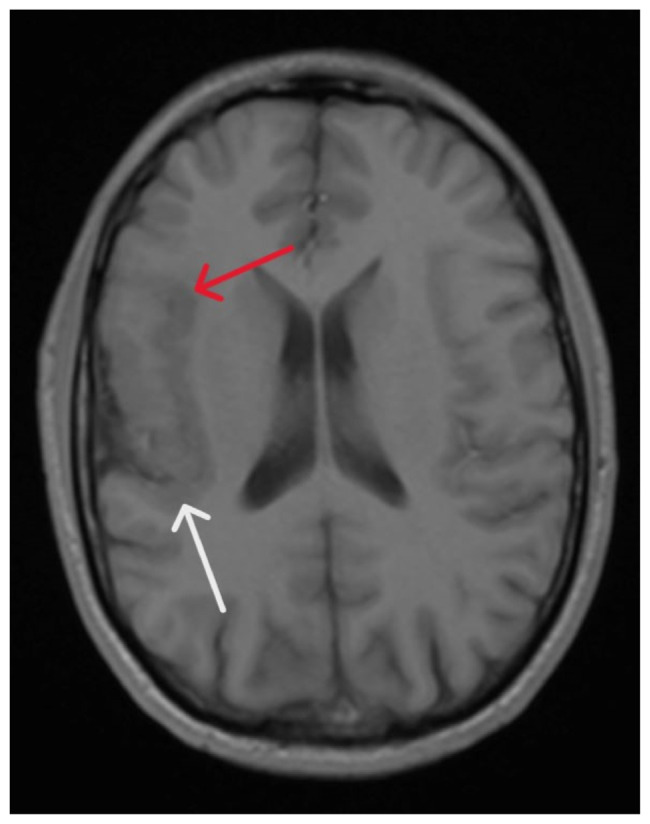

We present the case of a young man in his early thirties who sought medical attention after a witnessed seizure episode. His drug screen revealed the presence of cocaine, marijuana, and benzodiazepines. To investigate any potential structural causes contributing to his seizure, we conducted an MRI of the brain, which revealed polymicrogyria. This structural abnormality is strongly associated with seizures. This case emphasizes the importance of ruling out underlying structural causes of seizure disorders in patients with a history of drug abuse before recommending cessation of drug use.